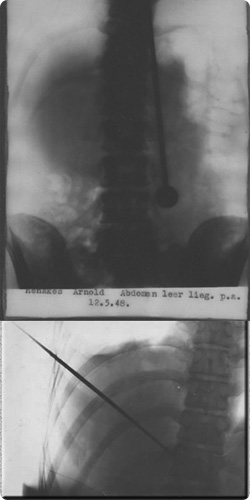

医師が剣を突き刺した状態でのX線検査を申し入れるとダヨは快く応じた

彼はこの現象を証明したかった訳ではないらしい 医師に行為の許可が欲しかったのだ

X線検査が行われた結果 ダヨの身体に剣が突き刺さっていることは もはや疑いようのない

事実であることが確認された 剣は確かに彼の幾つかの臓器を貫いていたのだ

ところがダヨには剣が突き刺さったことによる肉体的な影響も内臓へのダメージも

見受けられない 結局医師たちは検査を終えても首を傾げるばかりだった